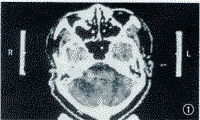

图1 A患者听神经瘤X-刀治疗前2 mm薄层CT平扫加增强,肿瘤直径达25.2 mm。

图2 A患者听神经瘤X-刀治疗后1年2 mm 薄层CT平扫加增强复查,听神经瘤直径17 mm。